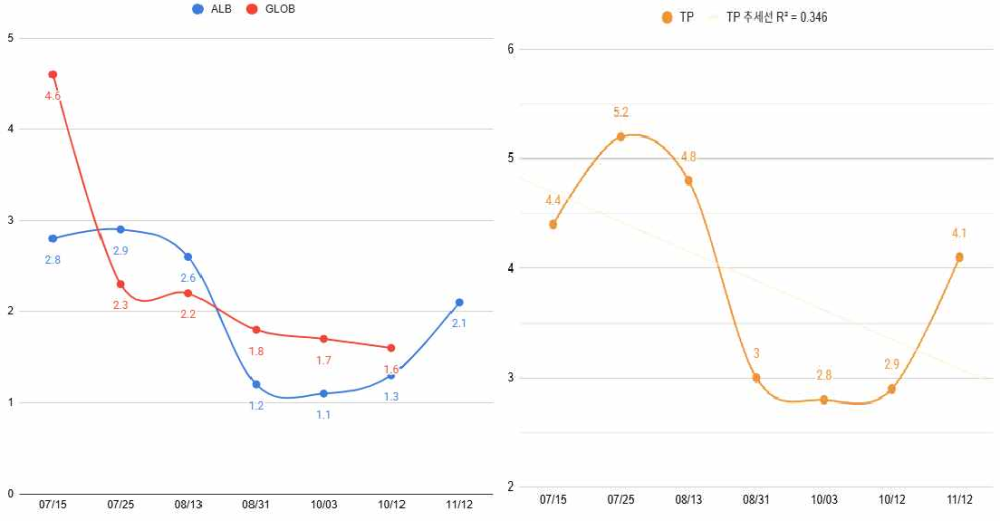

- 혈액 속 단백질 수치가 낮아진 상태(저알부민혈증)

이에 따라 초기 치료로는 장 염증과 면역 반응을 조절하기 위한 스테로이드 치료를 시작하였고, 간 기능 및 소화기 보호를 위해 간 보호제와 위산 억제제를 병행하였습니다. 장내 환경 조절을 위해 항생제를 사용하였으며, 저알부민혈증 개선을 위해 사람 알부민 수혈을 시행하였습니다.

입원 치료 후 증상이 다소 안정되면서 퇴원하였고, 스테로이드 기반 치료, 위장관 보호제, 간 보호제, 저지방 처방식(Hill’s i/d low fat)을 중심으로 관리에 들어갔습니다.

체중 감소는 있었으나 전반적인 컨디션을 고려해 스테로이드 감량(tapering) 을 조심스럽게 시작했습니다.

8월 31일 '재입원: 저알부민혈증 재발'

스테로이드 감량 이후,

- 저알부민혈증 재발

저지방 식이 유지, 식이량 및 단백원 조절, 약물 구성 재검토를 진행하며 수치보다 아이의 전반적인 상태를 중심으로 치료 방향을 조정했습니다.

기존 치료만으로는 충분한 반응이 어려워, Cyclosporine, Octreotide, 지사제 및 장 보호제 등을 추가하여 면역 조절과 림프관 압력 완화를 동시에 목표로 관리했습니다.

[혈액 검사]

또한 PLE(단백 소실성 장질환) 관리에 있어서는 혈액검사 수치, 특히 알부민 수치에만 지나치게 집중하기보다는 아이의 체중 변화, 전반적인 컨디션, 식욕과 임상 증상을 함께 종합적으로 평가하는 것이 중요합니다.

알부민 수치가 다소 낮더라도 임상적으로 안정적인 경우도 많으며, 반대로 수치 개선만을 목표로 면역억제제를 과도하게 증량할 경우 오히려 합병증으로 상태가 악화되는 사례도 적지 않습니다.